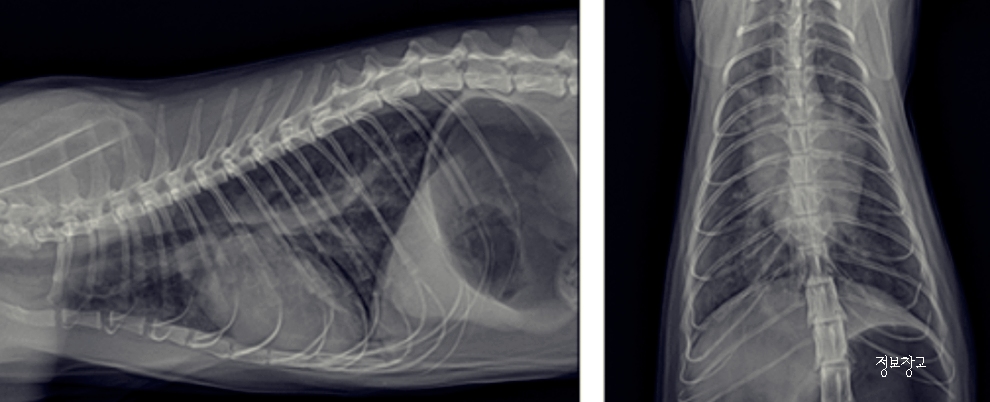

② 고양이 천식

특징

- 낮게 엎드린 자세

- 목을 길게 빼고 ‘흡흡’ 소리

- 숨이 가쁜 느낌

⑤ 심장 질환

- 잦은 기침

- 숨 가쁨

- 쉽게 지침

⑥ 폐렴·흉강 문제

- 기침 + 무기력

- 호흡 소리 거침

- 식욕 저하